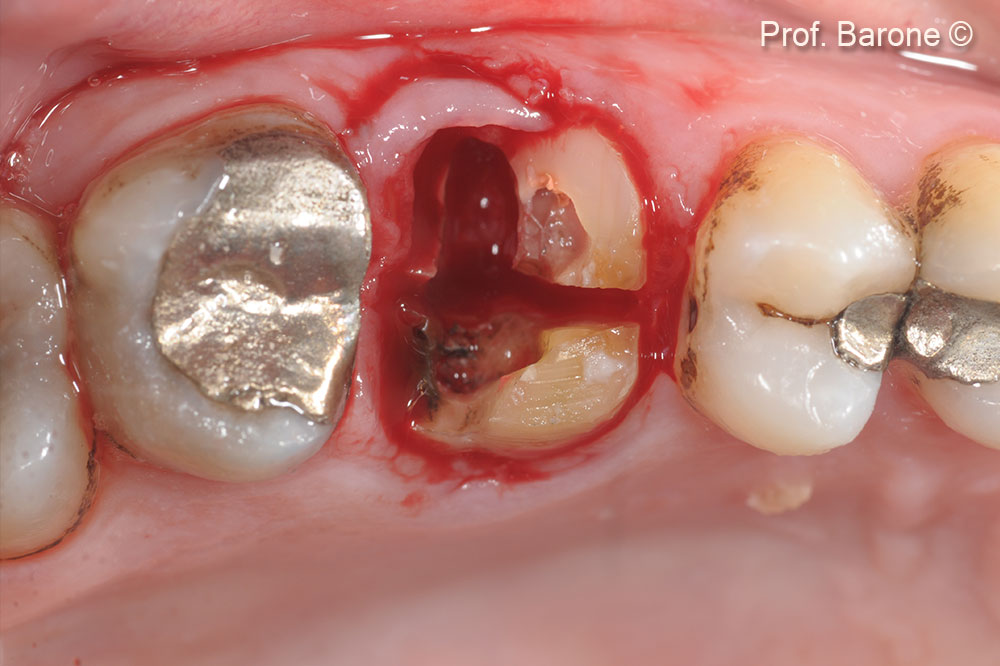

Implant Placement after 5 months